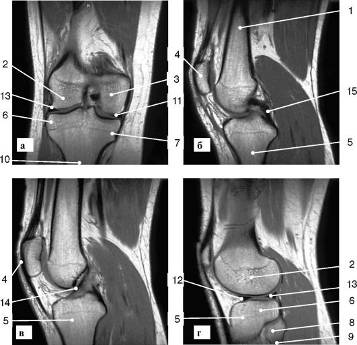

Внедрение МР-томографии позволило значительно улучшить качество исследования суставов.

Рис. 7. МР-томограмма коленного сустава (а - фронтальный срез; б, в - сагиттальные срезы; г - парасагиттальный срез): 1 - бедренная кость; 2 - латеральный мыщелок бедренной кости; 3 -медиальный мыщелок бедренной кости; 4 - надколенник; 5 - большеберцовая кость; 6 - латеральный мыщелок большеберцовой кости; 7 - медиальный мыщелок большеберцовой кости; 8 - головка малоберцовой кости; 9 - шейка малоберцовой кости; 10 - межмыщелковое возвышение; 11 - медиальный мениск, передний рог; 12 - латеральный мениск, передний рог; 13 - латеральный мениск, задний рог; 14 - передняя крестообразная связка; 15 - задняя крестообразная связка

Такое исследование позволяет врачам визуализировать не только окружающие сустав мышцы и связки, но и суставную сумку, покрывающие хрящи, мениски и определять количество жидкости в суставах (рис. 7).